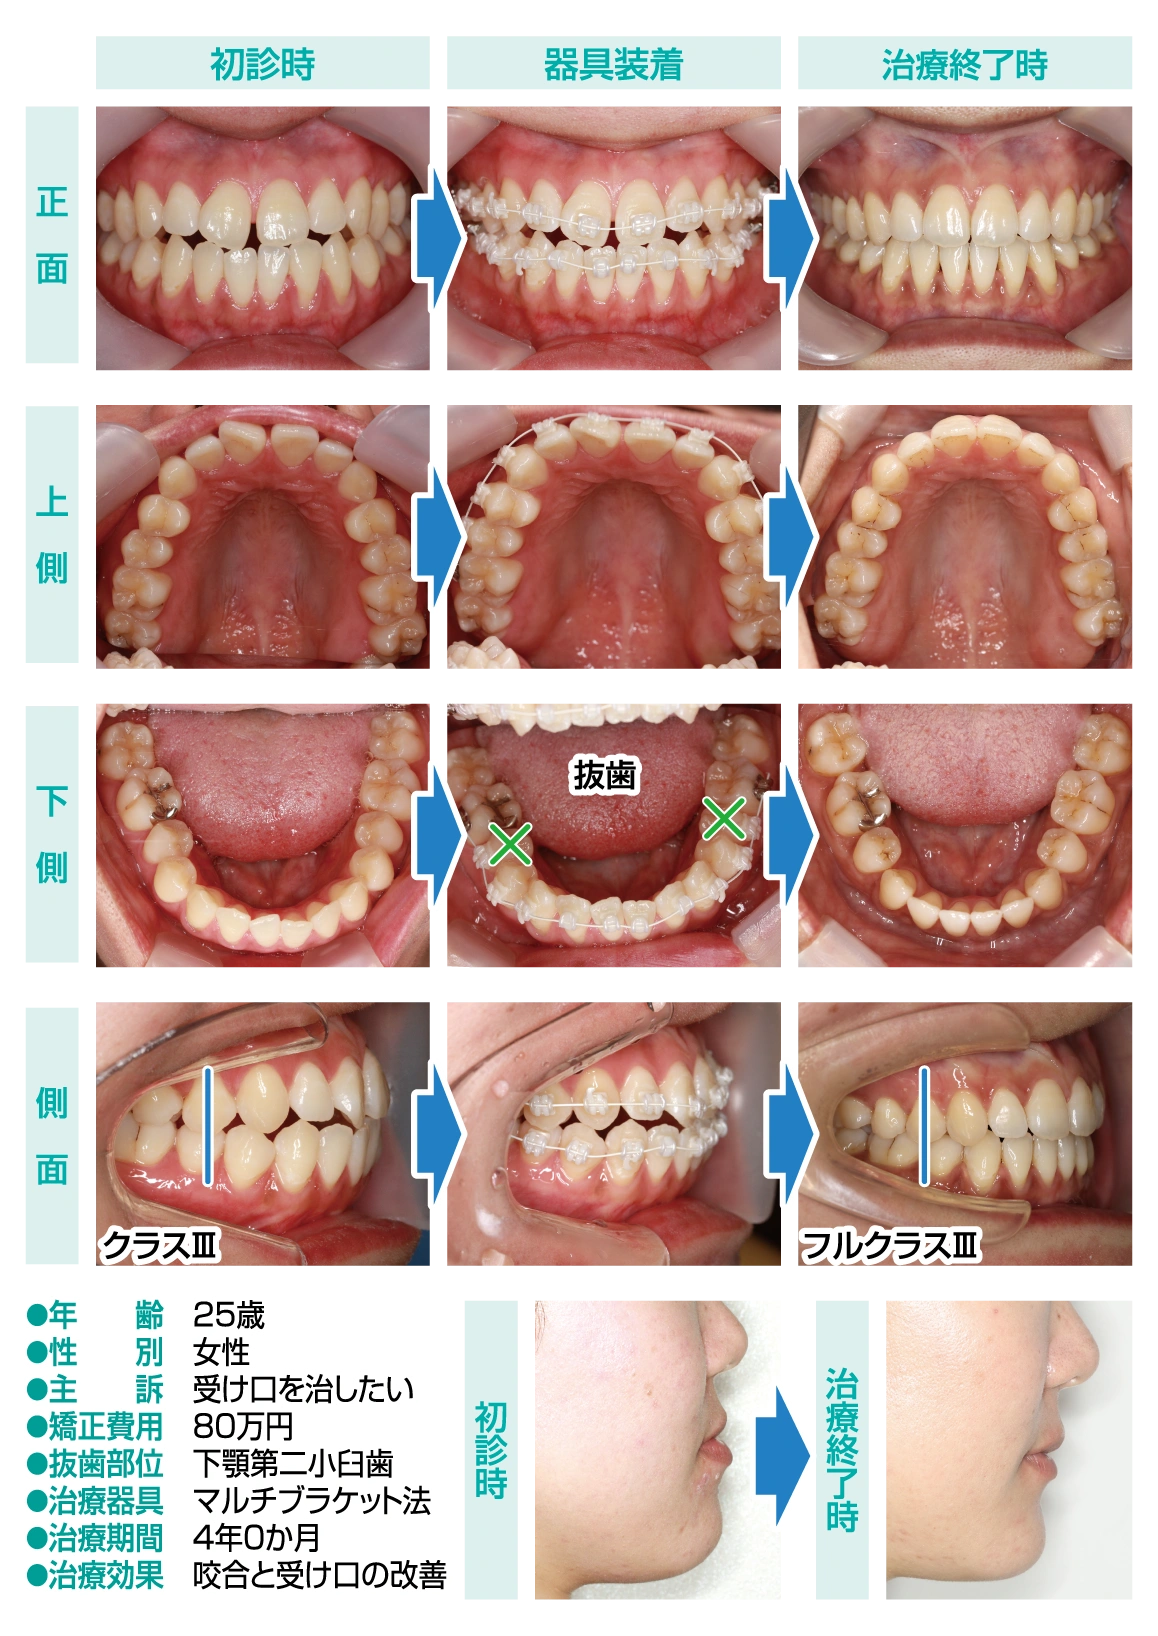

Vol.149 下顎小臼歯抜歯を伴うクラスⅢ症例

今回の患者様は、受け口を治したいと来院されました。クラスⅢの噛み合わせのため、下顎臼歯が上顎臼歯に対して前方に位置しています。

クラスⅢの場合、歯性の要素よりも骨格性の要素が強ければ、下顎骨切りの手術を併用した外科的矯正治療も検討しますが、患者様は手術はしたくないと言われたため、通常の矯正治療を検討しました。

当初の治療方針は、非抜歯にて下顎臼歯を後方に移動して、I級関係の咬合確立を目指しました。

矯正治療がスタートし、下顎臼歯の後方移動を試みたのですが、思うように動かず、その煽りをうけた下顎前歯が唇側傾斜してしまい、クラスⅢ特有の受け口がさらに悪化してしまいました。そのため、途中から治療方針を変更して、下顎第二小臼歯の抜歯を行い、フルクラスⅢの咬合様式となるよう治療を進めていく事にしました。

しかし、臨床的にフルクラスⅢに仕上げるのはかなり難しいため、下顎にアンカースクリューを埋入して、咬合状態の緊密化を図りながら治療を進めていった結果、4年という治療期間を要してしまいましたが、安定した咬合が得られ、口元の陥凹感も改善されました。

- 年齢・性別

- 25歳 女性

- 治療期間

- 48ヶ月

- 抜歯

- 下顎両側5番

- 治療費

- 80万円

- 治療内容

- 全顎矯正治療